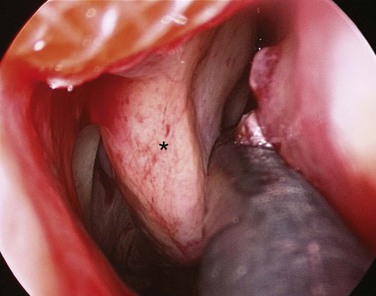

Hereditary hemorrhagic telangiectasia (HHT) is an autosomal-dominant multisystemic disorder characterized by telangiectasia that affects cutaneous and mucosal surfaces and arteriovenous malformations in the pulmonary, cerebral, and hepatic circulations (Fig. 42-23). The most common symptom in this population is epistaxis, which affects more than 90% of individuals. The severity of attacks is variable, and episodes of epistaxis can be functionally and socially debilitating for the patient and may require frequent hospital admission; in addition, a set of patients exists for whom the bleeding is intractable.99 Many methods of treatment for epistaxis as a result of HHT have been described in the literature; these include medical strategies, such as the use of hormonal manipulation and antifibrinolytic agents, as well as surgical options, which include laser coagulation (Fig. 42-24),100 septodermoplasty,101 and nasal closure,102 but no one method has proved itself entirely successful or without significant side effects.

A recent prospective study by Hitchings and colleagues99 investigated the effect of various surgical options on quality of life scores in these patients. The authors have concluded that nasal closure should be offered to patients with moderate to severe epistaxis that has proved unresponsive to other treatment options (bipolar or laser coagulation treatment, septodermoplasty), and subjectively 88% (7/8) of patients treated with nasal closure reported a complete cessation of their nosebleeds. Closure of the nasal cavity, the Young procedure, is based on the principle that the absence of desiccating airflow through the nasal cavity prevents the initiation of mucosal breakdown overlying the fragile telangiectasias.102 An alternative to nasal closure is the use of nasal obturators.103 In recent years, the monoclonal antibody bevacizumab has been advocated in HHT for intractable epistaxis, with use both topically104 and by local injection.105-107 In addition, some evidence supports the use of tamoxifen to reduce the need for blood transfusions.108